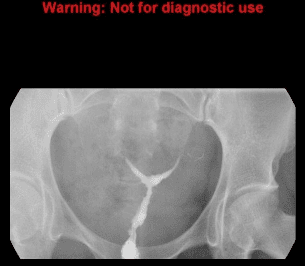

Hình ảnh tử cung hình cung trên hình chụp X-quang tử cung vòi trứng chỉ thấy hiện diện một khoang nội mạc tử cung với một vết lõm rộng hình yên ngựa của đáy tử cung.

Hình 2: Hình ảnh tử cung hình cung trên phim chụp tử cung vòi trứng